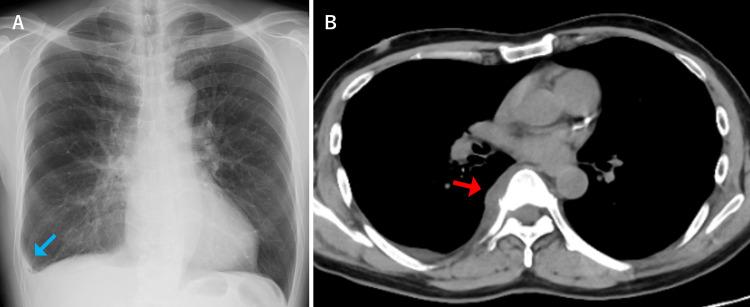

Pyogenic spondylitis typically presents with back and neck pain, fever, and fatigue. Sharp chest pain upon deep breathing, commonly associated with pleurisy, is not a typical manifestation of pyogenic spondylitis. We report a case of pleuritic chest pain as the initial presentation of pyogenic spondylitis. A 62-year-old male patient presented with a one-week history of right-sided pleuritic chest pain and fever. Chest computed tomography (CT) revealed a right pleural effusion. The patient was initially treated for bacterial pleurisy without improvement and subsequently developed back pain. Blood cultures yielded methicillin-resistant ( ​​​​). Additional thoracic spine magnetic resonance imaging (MRI) demonstrated pyogenic spondylitis with abscess formation on the right side of the vertebral body. The final diagnosis was pyogenic spondylitis that had progressed and spread inflammation to the pleura. This case highlights that pyogenic spondylitis can cause secondary pleurisy due to extension of inflammation to adjacent structures, a possibility that should be recognized. When  bacteremia is detected during the course of pleurisy, clinicians should consider secondary pleurisy and perform imaging studies to evaluate for pyogenic spondylitis.

摘要

化脓性脊柱炎通常表现为背部和颈部疼痛、发热及乏力。深呼吸时出现的尖锐胸痛,通常与胸膜炎相关,并非化脓性脊柱炎的典型表现。我们报告一例以胸膜炎性胸痛为首发表现的化脓性脊柱炎病例。一名62岁男性患者,有一周右侧胸膜炎性胸痛及发热病史。胸部计算机断层扫描(CT)显示右侧胸腔积液。该患者最初按细菌性胸膜炎治疗但无改善,随后出现背痛。血培养检出耐甲氧西林(此处原文缺失内容)。额外的胸椎磁共振成像(MRI)显示化脓性脊柱炎,椎体右侧有脓肿形成。最终诊断为化脓性脊柱炎,炎症进展并蔓延至胸膜。该病例强调化脓性脊柱炎可因炎症蔓延至相邻结构而导致继发性胸膜炎,这一可能性应得到认识。当在胸膜炎病程中检测到菌血症时,临床医生应考虑继发性胸膜炎并进行影像学检查以评估是否存在化脓性脊柱炎。